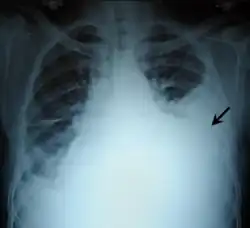

| Chest X-ray showing left sided hemothorax (arrowed) | |

Chest X-ray

A chest X-ray is the most common technique used to diagnosis a hemothorax.[23] X-rays should ideally be taken in an upright position (an erect chest X-ray), but may be performed with the person lying on their back (supine) if an erect chest X-ray is not feasible. On an erect chest X-ray, a hemothorax is suggested by blunting of the costophrenic angle or partial or complete opacification of the affected half of the thorax. On a supine film the blood tends to layer in the pleural space, but can be appreciated as a haziness of one half of the thorax relative to the other.[5] A small hemothorax may be missed on a chest X-ray as several hundred milliliters of blood can be hidden by the diaphragm and abdominal viscera on an erect film. Supine X-rays are even less sensitive and as much as one liter of blood can be missed on a supine film.[24]